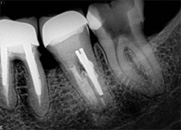

antes depois